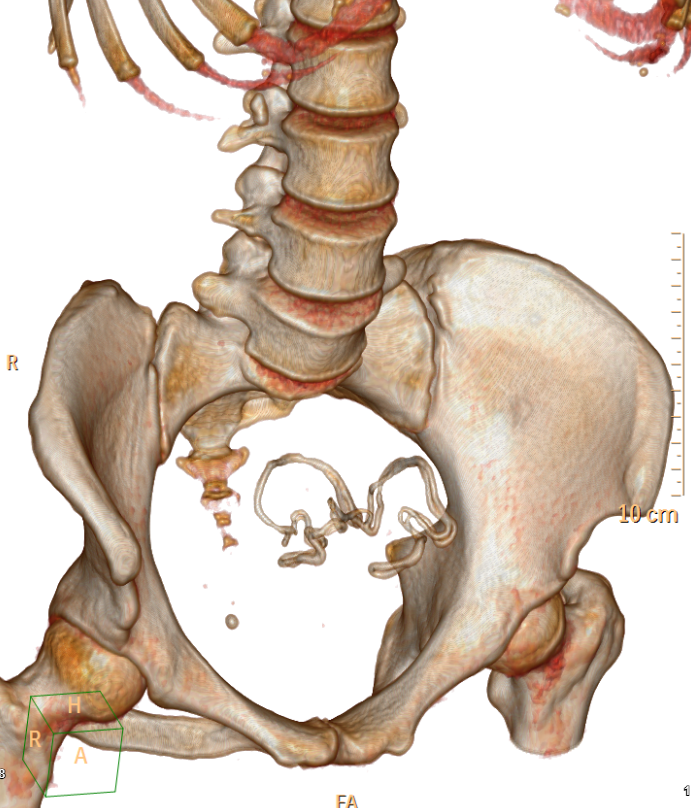

Abdominal CT With IV & Rectal Contrast

- Evidence of 9 X 7cm thick wall pelvic collection, contains gas, and linear metallic structure, markedly compressing sigmoid colon with edema in the wall, no leak of rectal contrast to collection, multiple inflammatory LNs, picture is suggestive of gossipbyoma.